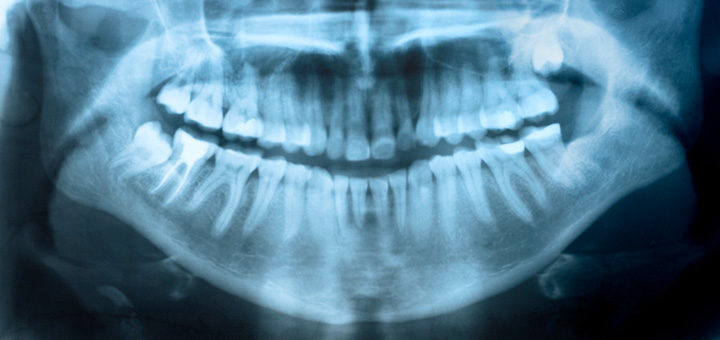

Full Mouth Reconstruction Full Mouth Reconstruction, also termed as Full Mouth Rehabilitation or Full Mouth Restoration, is a procedure of of rebuilding and restoring the teeth in the upper and lower jaws. The procedure...